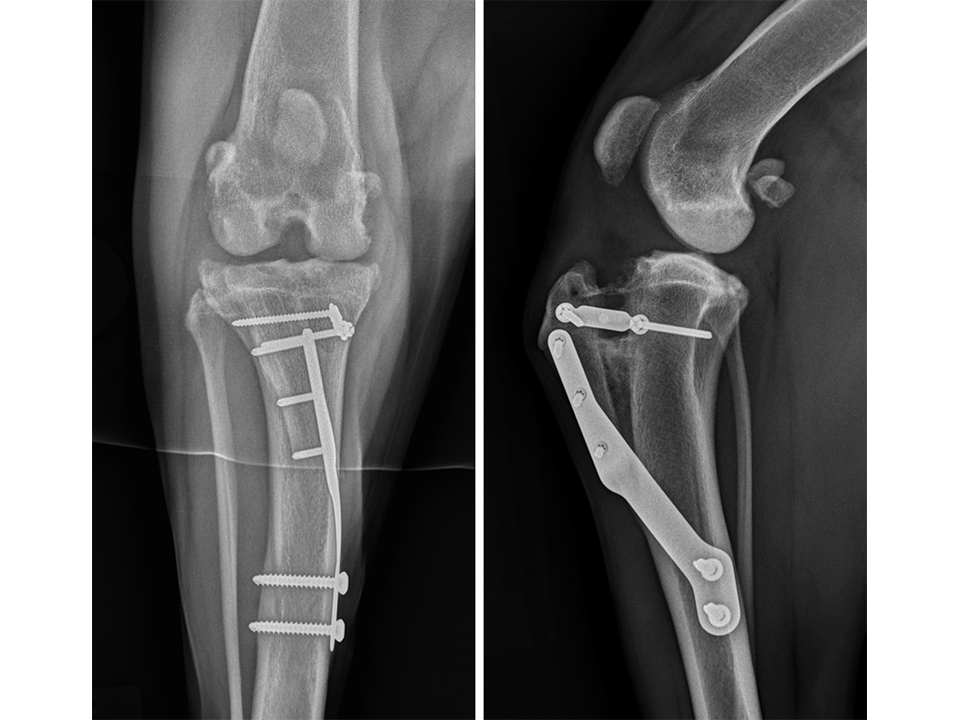

Immediate postoperative radiographs (Fig 11) revealed satisfactory implant and osteotomy positioning with the patella appropriately positioned within the femoral sulcus. There was no laxity in CrTT and the patella could not be luxated. Radiographs obtained 10 weeks postoperatively (Fig 12) revealed no evidence of implant-associated complications and smooth osseous proliferation bridging the osteotomy gap. Osteoarthritic changes within the joint were mildly progressive. Clinically at this stage, no pelvic limb lameness was evident. The range of motion of the right stifle joint was within normal limits. The stifle was stable in CrTT and the patella could not be luxated. No pain response was noted with the physical examination.